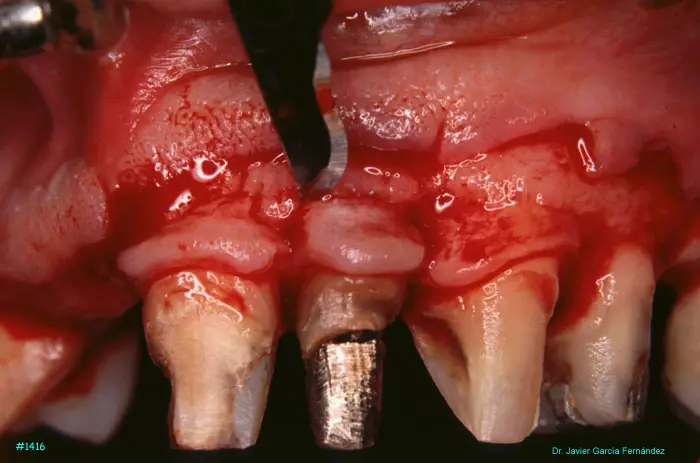

Atlas of Surgical Techniques in Periodontics. Chapter III. Atlas de Técnicas Quirúrgicas en Periodoncia